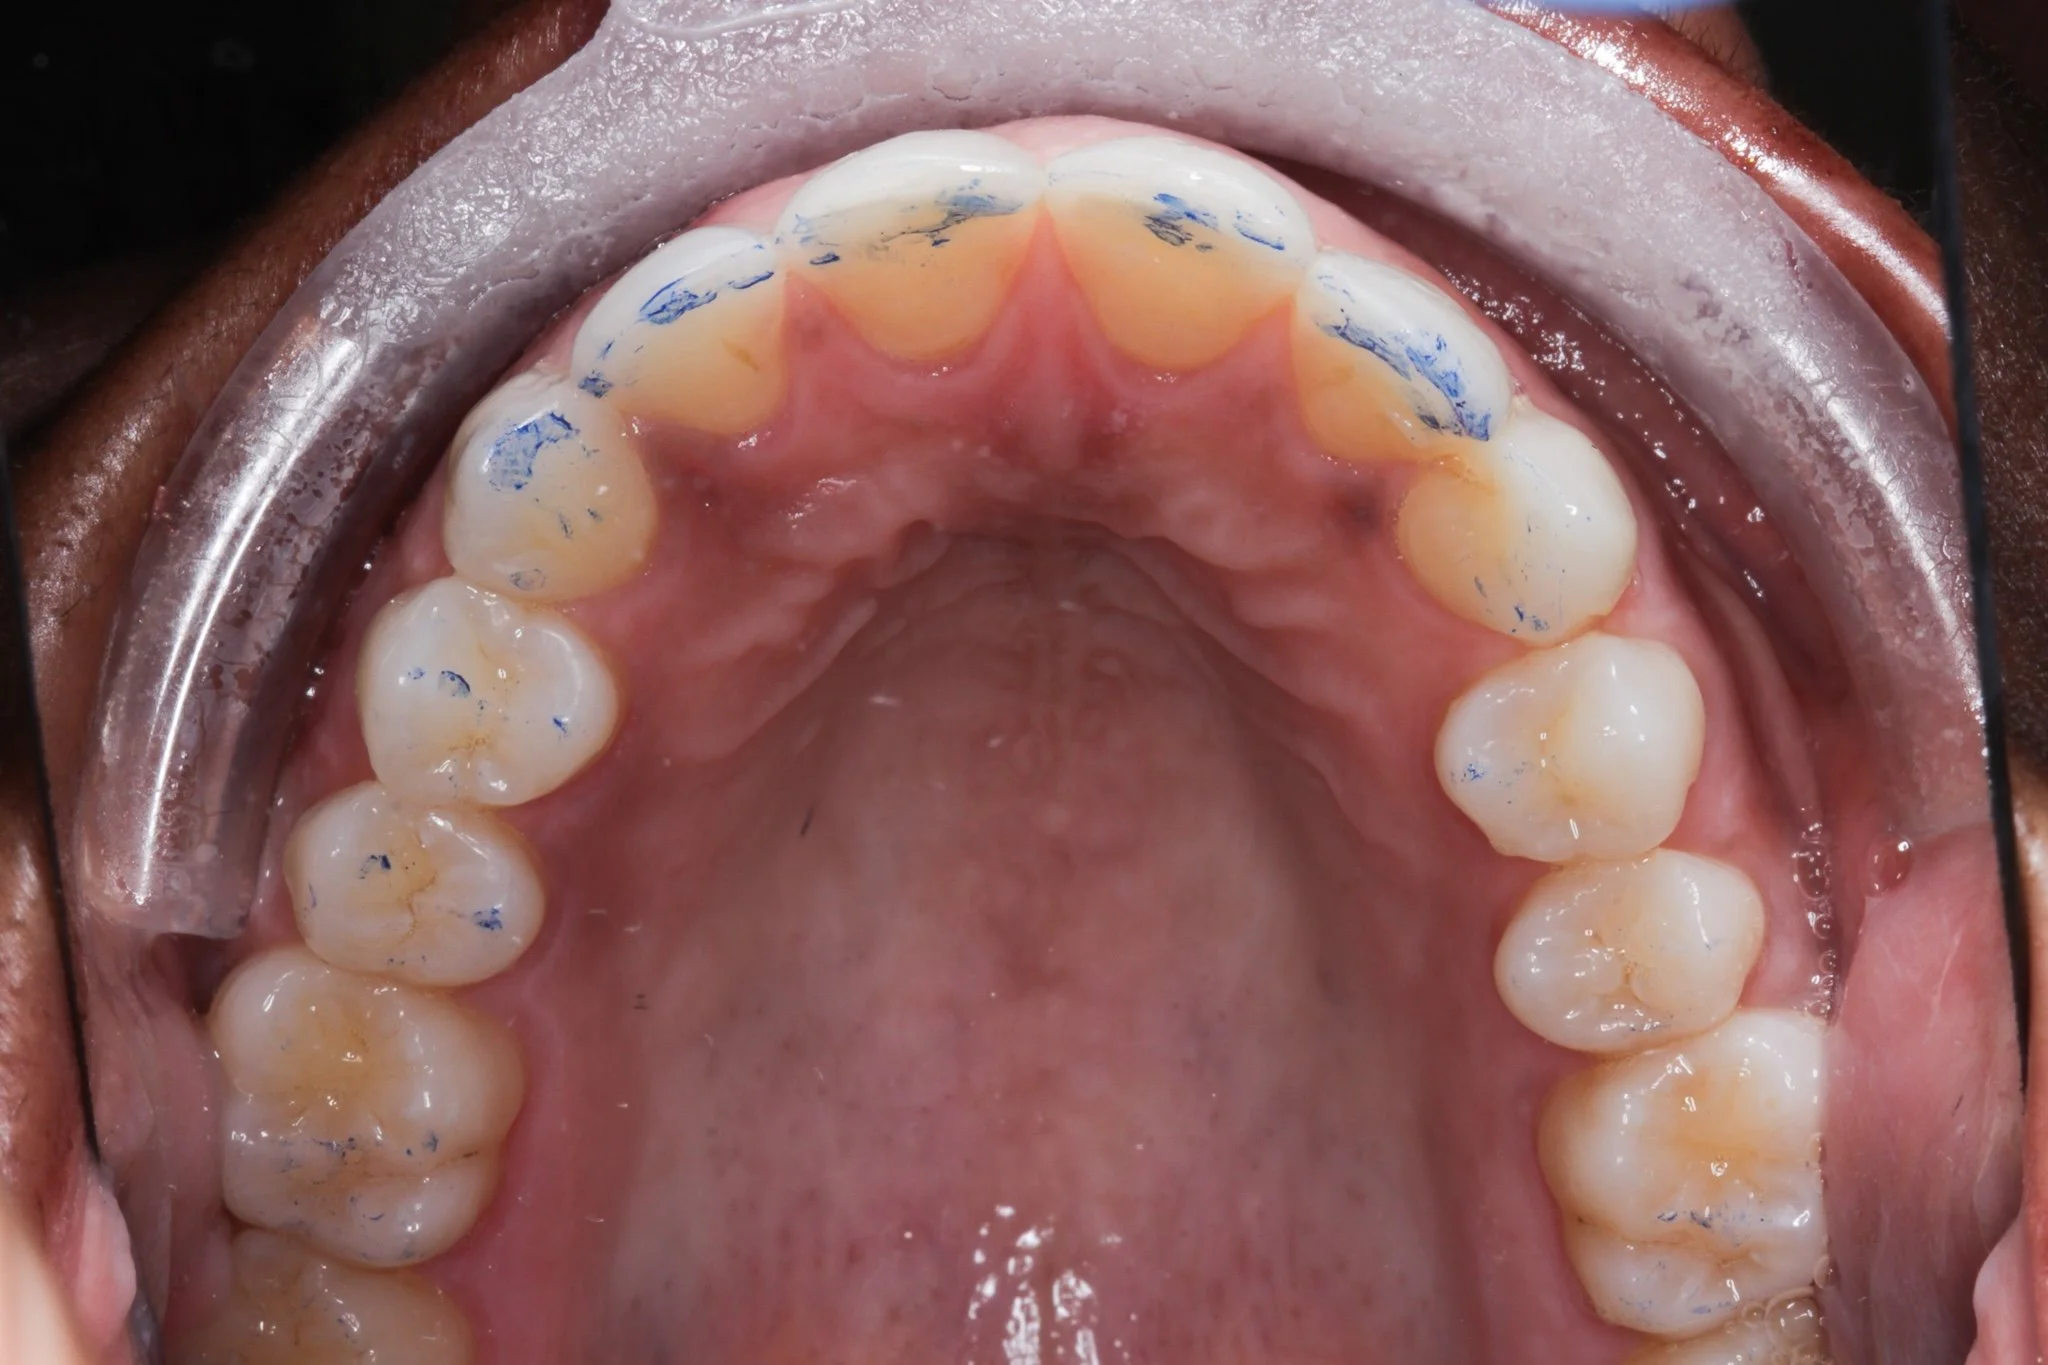

Your dentist will use special articulating paper that marks up specifically where you bite on your teeth, and they will be able to precisely adjust the onlayto fit your mouth.

Articulating paper used to show where exactly your teeth are touching when you bite